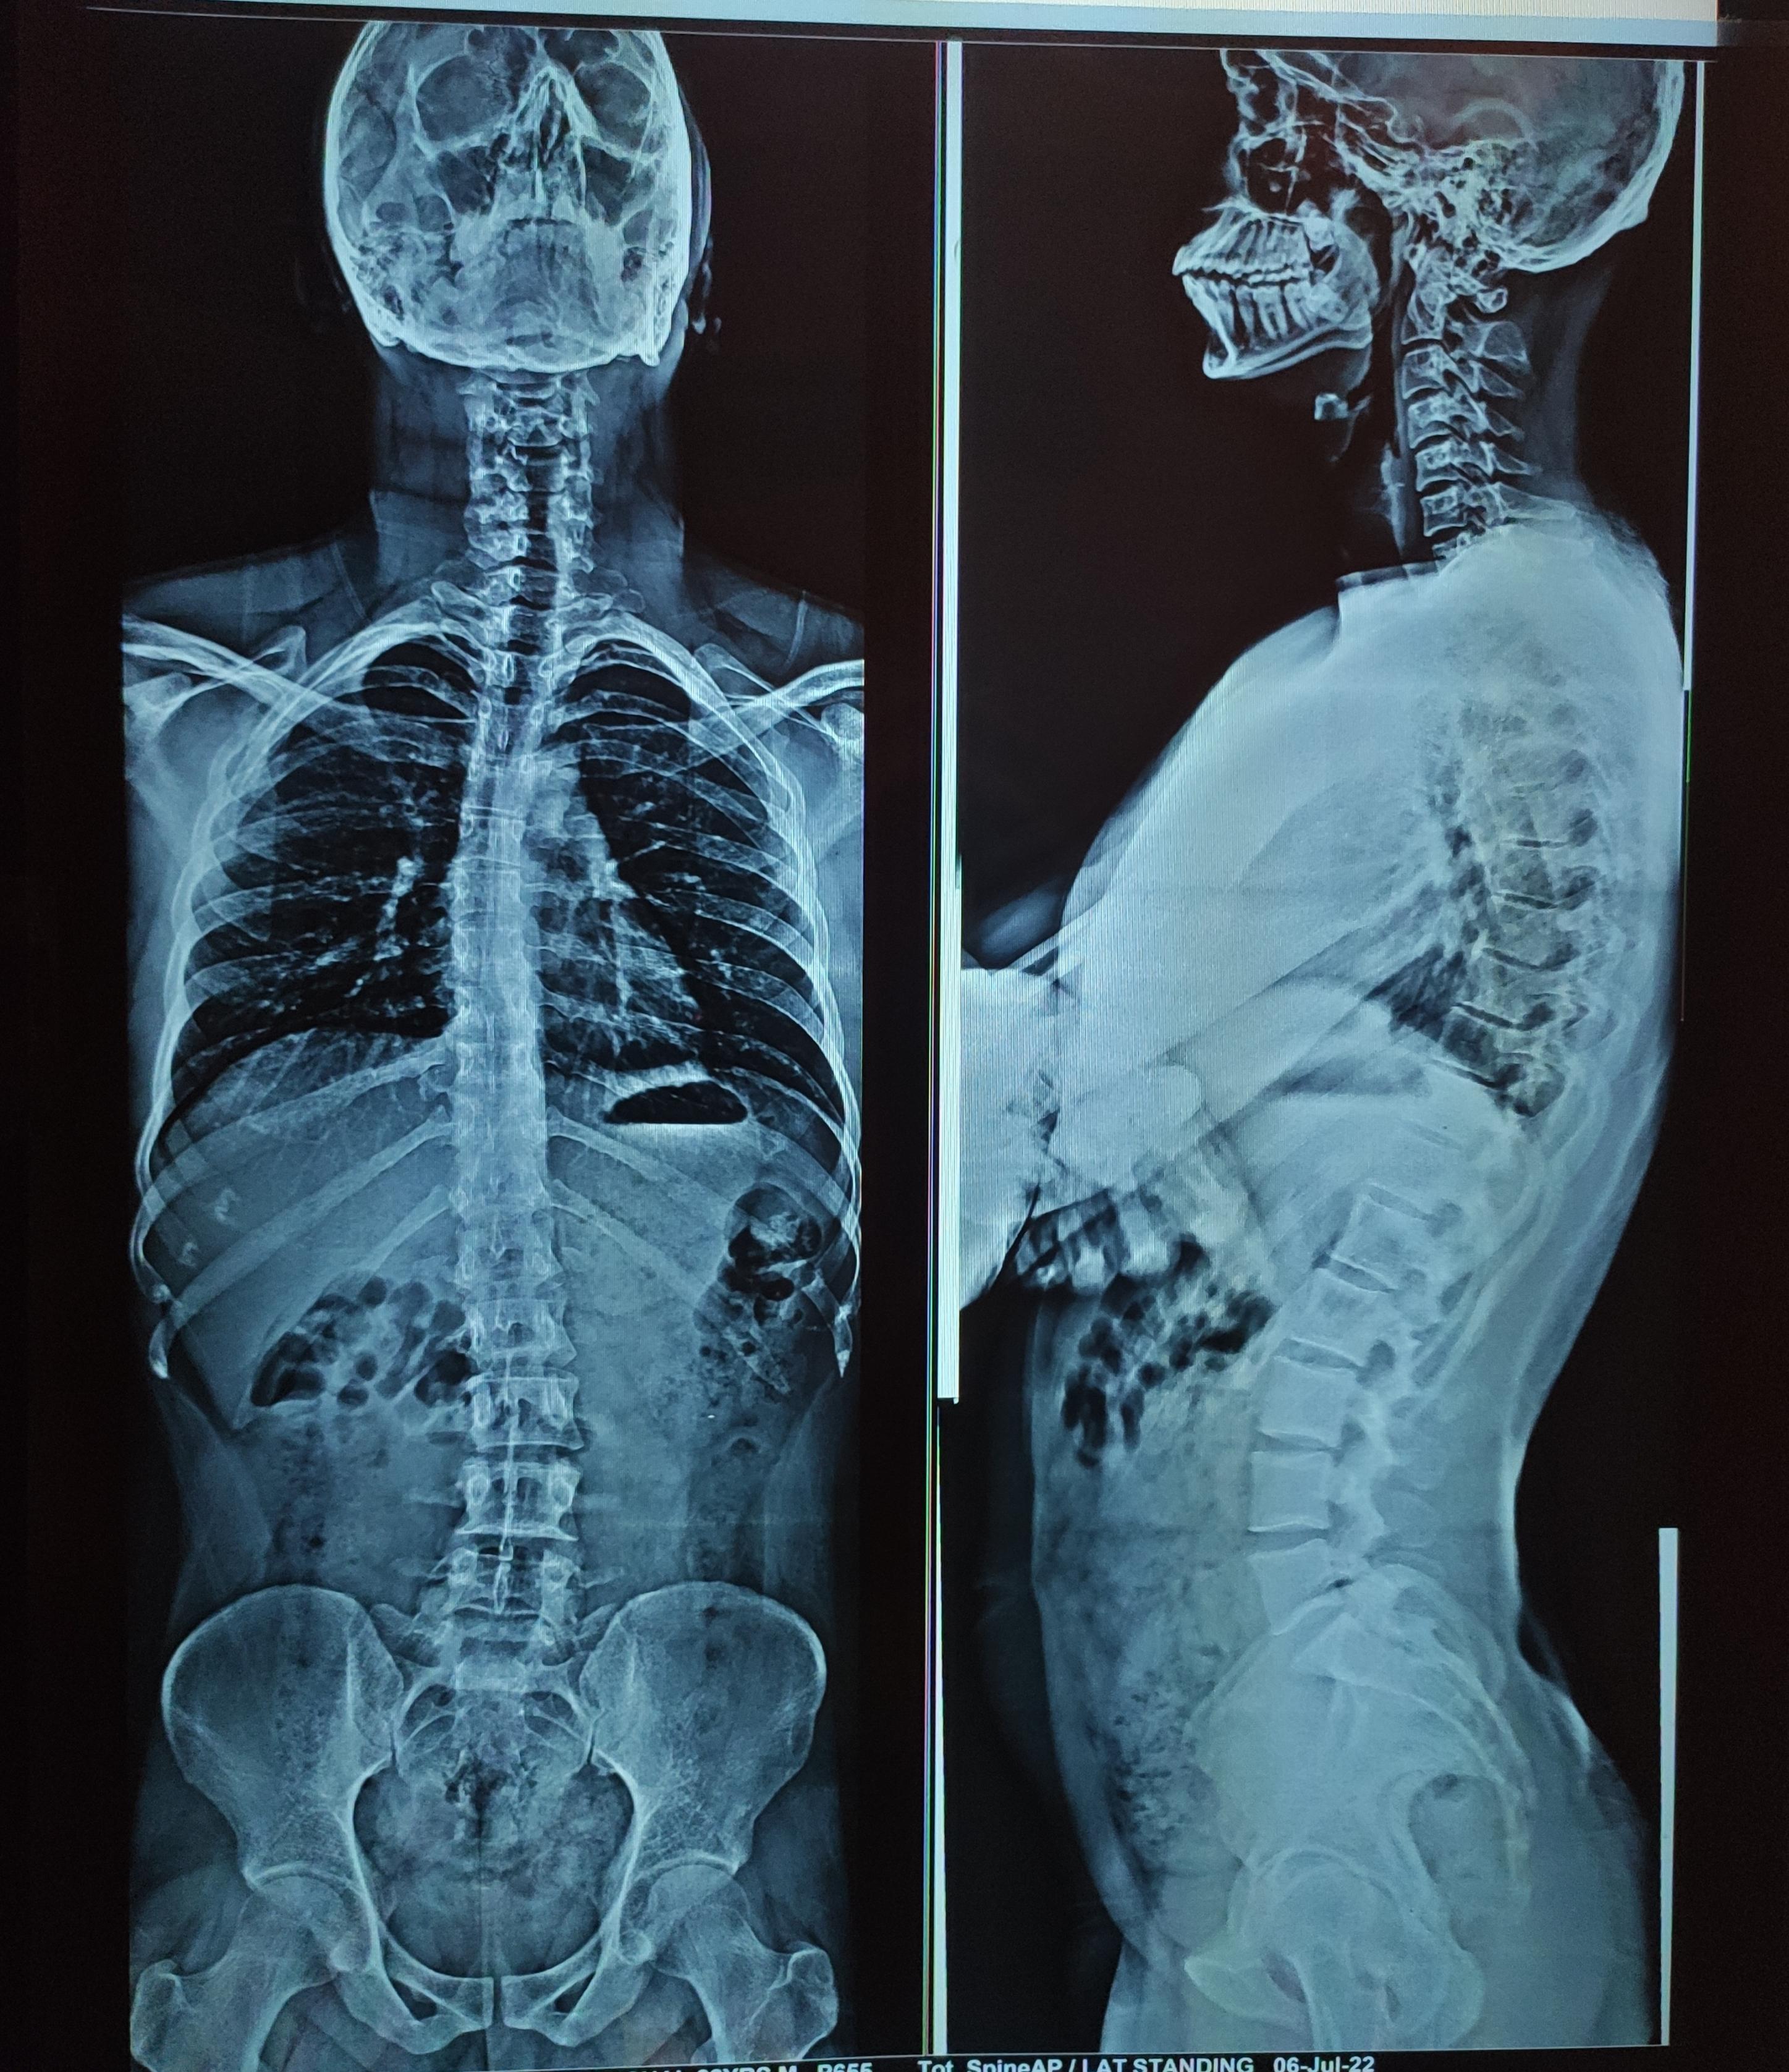

Is it a major scoliosis ?. Can i do heavy weightlifting with that much Is Weightlifting Bad For Scoliosis This helps keep activities safe and improves exercise performance. It’s a common misconception that lifting weights and participating in resistance training is harmful for scoliosis patients. In particular, avoid heavy weightlifting workouts that compress the lumbar spine, such as squats, dead lifts and overhead presses. Weightlifting has the potential to be quite a damaging pastime for people with scoliosis, but. Is Weightlifting Bad For Scoliosis.